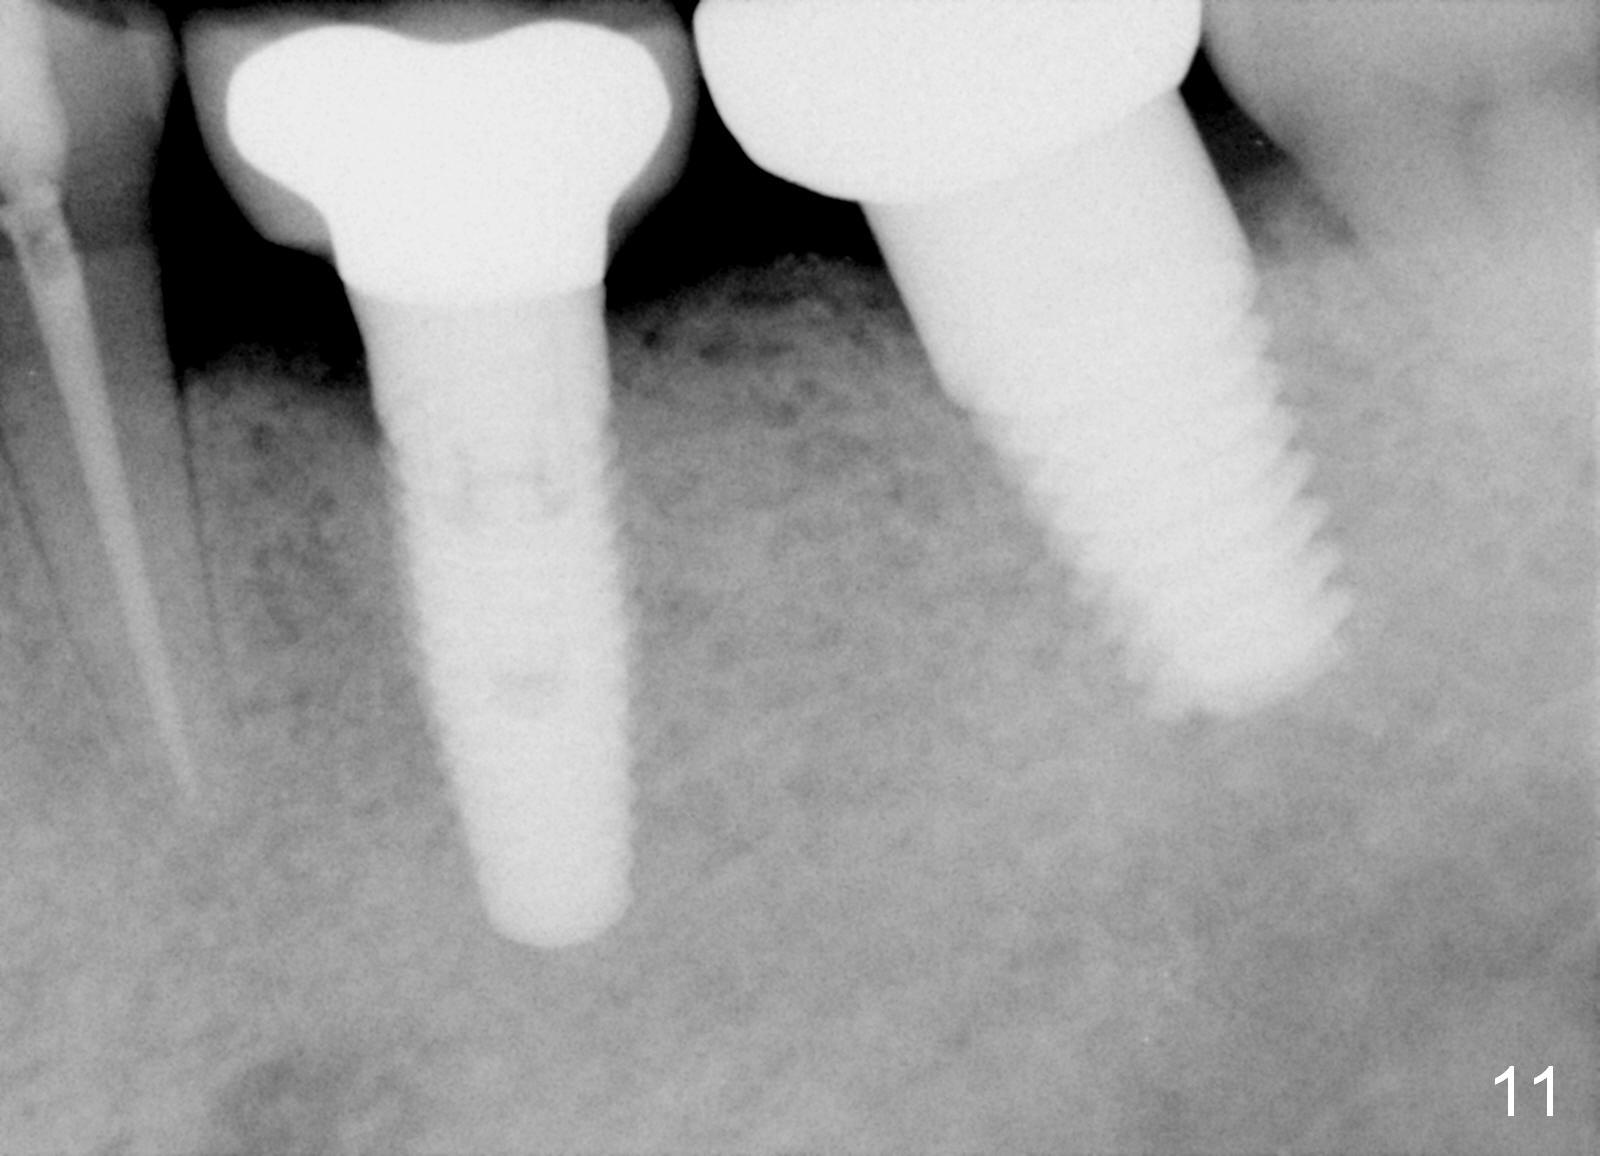

The septum of the socket is thin (Fig.3*), and easily removed, leaving a large socket. Osteotomy is initiated with 2 mm pilot drill in the middle of the socket, slightly mesiolingual, since the buccal and distal bone is low and defective. Reamers (2.5 to 4 mm in diameter) are sequentially used to enlarge osteotomy and harvest autogenous bone (Fig.4 (3 mm reamer in place). When 5 mm tap is placed, there is no stability. Six mm tap gains some stability, but the socket is not closed. Seven mm tap achieves strong stability and is closing the socket (Fig.5). Ultimately a 7x14 mm implant is placed with insertion torque more than 60 Ncm (Fig.6). The implant almost obliterates the socket (Fig.7). The harvested autogenous bone is placed in the buccal and distal aspects of the socket before Chromic gut suture (4-0) is placed distally. Fig.8,9 show the healing socket 6 days and 1.5 months postop, respectively. Osteointegration appears to occur in 2.5 months (Fig.10, compare to Fig.6). Bone level remains the same 1 year post cementation (Fig.11).